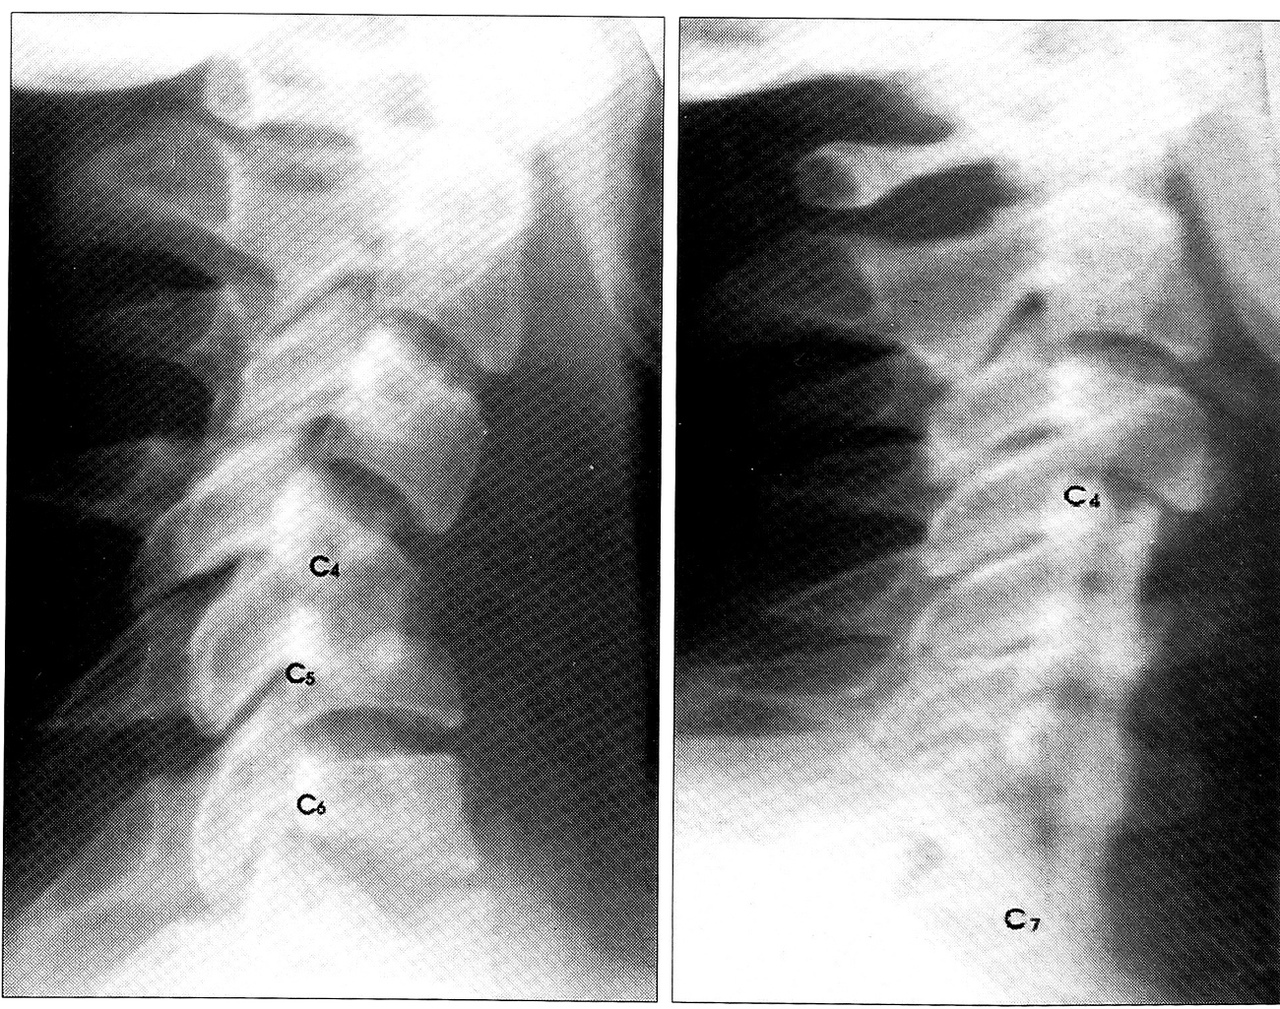

На спондилограммах (рис. 2, а): массивный деструктивный процесс в телах С4-6 позвонков с их патологическим переломом и разрушением смежных замыкательных пластинок и дисков; очаги деструкции в задних отделах С4-6 позвонков; кифотическая деформация позвоночника в шейном отделе. На рентгенограмме грудной клетки — левосторонняя пневмония. Неврологически: синдром Горнера слева, снижение глоточного рефлекса. Значительно снижена сила в левой руке, имеется гипотрофия мышц левого плеча, предплечья. Рефлексы с рук D > S. Анализ крови: СОЭ 60 мм/ч, НЬ 107 г/л, эр. 3,6*1012/л, л. 20,6*109/л. Анализ мочи: белок 0,090%, л. 60-80 в поле зрения, цилиндры гиалиновые.

При осмотре через 10 лет: жалоб нет, движения в шейном отделе позвоночника в полном обьеме, безболезненные, деформации не отмечается. Полный регресс неврологической симптоматики. На спондилограммах шейного отдела (рис. 2, б) определяется перестроившийся костный трансплантат на уровне СЗ-5, соединяющий в единый костный блок остатки тел позвонков.

Рис. 2. Спондилограммы больного Б. а — до операции: деструкция С4—6 позвонков; б — через 10 лет после операции: костный блок С4~7 позвонков.